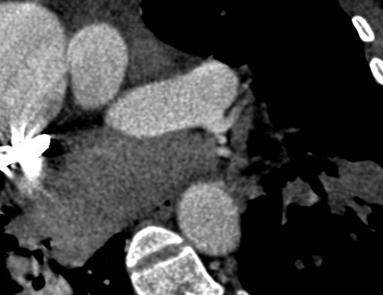

Persistent truncus arteriosus is an uncommon complex congenital heart disease. Without surgical intervention, the prognosis is not good. Very few untreated cases of truncus arteriosus survive to maturity. We report an exceptional case of uncorrected truncus arteriosus surviving into adulthood of type a3 variant -van praagh classification as a 26-year-old male who had well tolerated dyspnea since birth. Our patient showed a single(right) pulmonary artery arising from the common arterial trunk supplying the right lung and absent main and left pulmonary artery with collateral supply to the left lung consistent with the truncus arteriosus type a3-van praagh classification